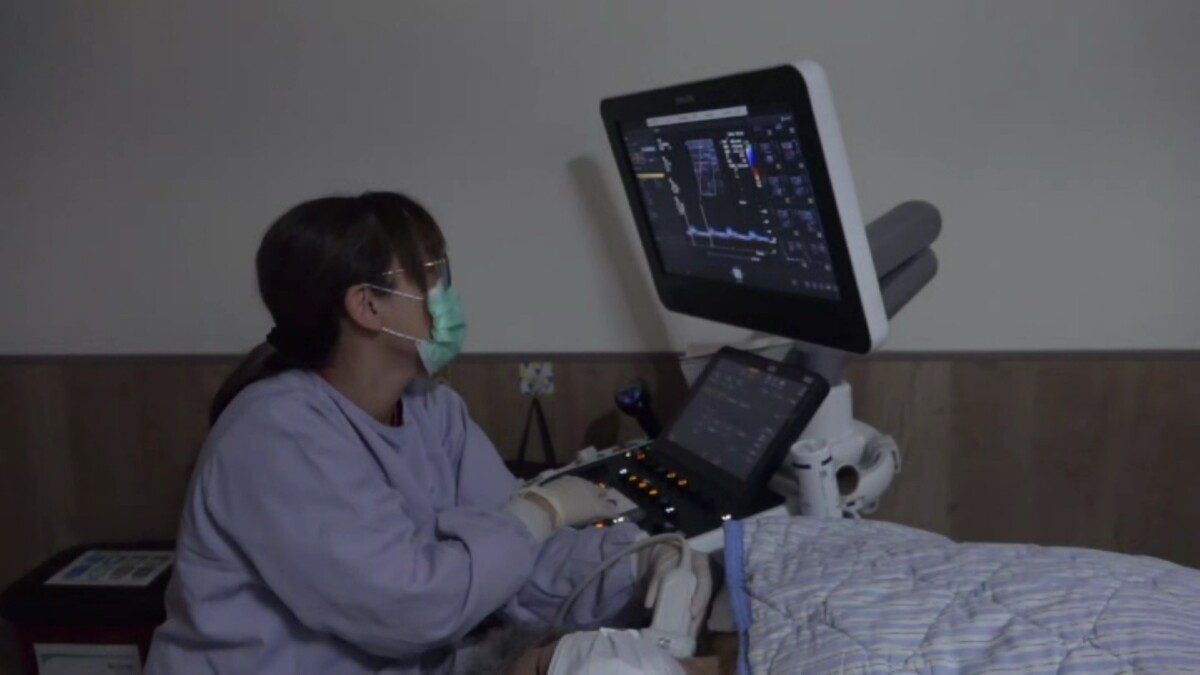

彰化醫院急診洪子文醫師指出,魏女士到院後經電腦斷層檢查,腦部無異常,僅後腦有撞傷,後續轉神經內科做頸動脈超音波、腦波及24小時心電圖檢查,也未發現心臟或腦部問題。魏女士表示,醫師提醒她平日注意情緒控制,之後就未再發生昏厥。